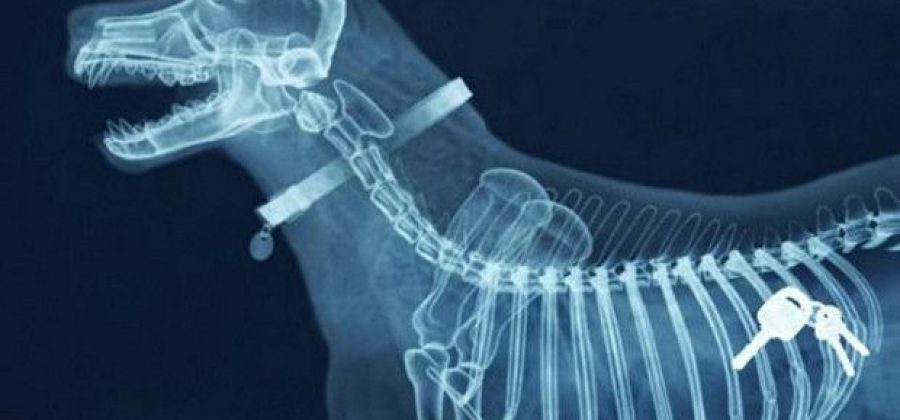

Рентгенография применяется в ветеринарии для выявления травм, заболеваний костей и суставов, патологий грудной и брюшной полости, а также для диагностики инородных тел. Она помогает определить переломы, вывихи, опухоли, воспалительные процессы, увеличение органов и другие аномалии.

Полученные рентгенограммы анализирует ветеринарный врач-рентгенолог. Он оценивает форму, размеры, структуру и плотность органов и тканей. Важно понимать, что рентген — не всегда конечная стадия диагностики. Часто он становится первым шагом, за которым следуют УЗИ, КТ, МРТ или лабораторные исследования.

Например, при подозрении на опухоль снимок покажет тень или уплотнение, но для подтверждения диагноза потребуется биопсия. При травмах рентген помогает определить степень повреждения и выбрать тактику лечения — от фиксации до хирургической операции.